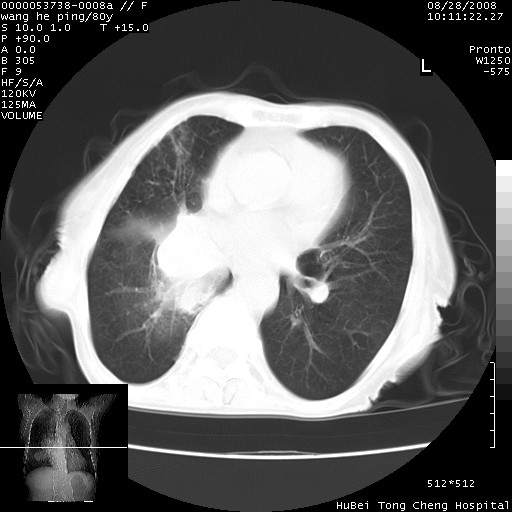

以下是引用黑白光影在2008-8-28 22:33:00的发言:[br]右肺中央型肺癌伴阻塞性肺炎,肺癌肺转移。

以下是引用lshx在2008-8-28 22:06:00的发言:[br]1.右肺中心型肺癌伴阻塞性肺炎,不除外双 肺早期转移。[br]2.心包积液。

以下是引用随光逐影在2008-8-29 7:40:00的发言:[br]1)右肺中心型肺癌伴阻塞性肺炎,肺内转移。2)心包积液(少量)。

以下是引用wqs571018在2008-8-28 21:56:00的发言:[br]右肺中心型肺癌伴阻塞性肺炎可能。

以下是引用liuyue在2008-8-28 22:46:00的发言:[br]1.右肺中心型肺癌伴阻塞性肺炎。[br]2.心包积液(少量)。